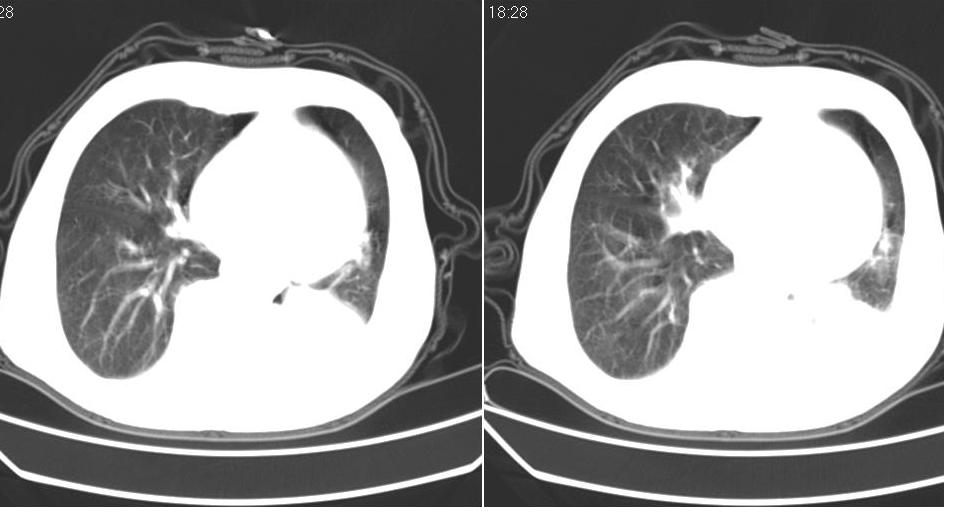

男 80岁,外院病人,有脑梗塞病史,近两个月发热,体温38.5度左右,抗炎后体温正常,药物停有发热。

左肺下叶略萎陷、实变,内可见含气支气管征。左舌叶、中叶亦见少许斑片状高密度区,边界不清。纵隔未见肿大淋巴结影。

考虑:1、肺感染;

2、建议严格抗炎治疗后复查。

左下肺体积缩小,密度增高,见片增密影。边界模糊,见支气管充气像,肺门纵隔无异示,心脏气管左移,左侧胸腔少量积液。考虑肺部感染伴部分肺不张[有脑梗塞病史坠积性肺炎可能]

左肺下叶体积缩小,成类楔形软组织影,其内可见部分含气支气管影,相应左侧肺门区未见明显肿块,考虑炎性病变,建议抗炎后短期复查